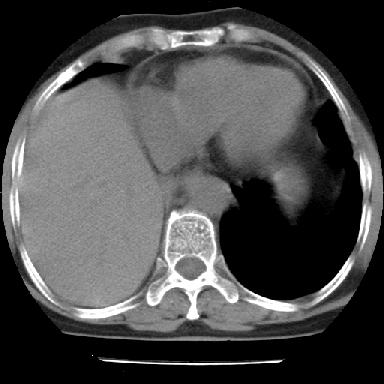

以下是引用swyyy2007在2007-4-13 15:31:00的发言:[br]右肺门下区肿块,右肺下叶支气管阻塞,右肺下叶不张,右侧大量胸腔积液,右肺中叶见结节状高密度影,边缘清,纵隔内见肿大淋巴结。首先考虑右下肺中心型肺癌伴右肺下叶不张、中叶、纵隔淋巴结转移。右侧胸腔积液。

以下是引用苯小孩在2007-4-13 16:20:00的发言:[br]1、右下肺中央型肺癌并阻塞性肺不张、肺内转移、胸椎右侧附件亦有转移<横断层面第8层>.[br]2、右侧胸腔积液.